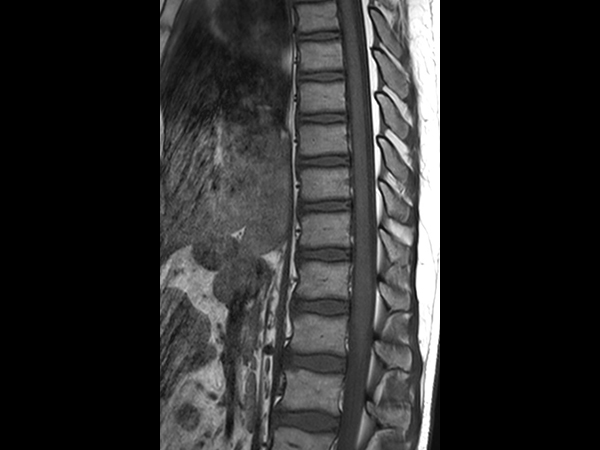

Sagittal T2w TSE (L-Spine)